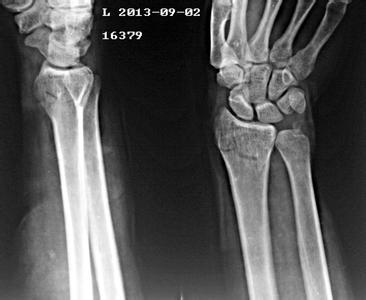

导读: 老年人的身体都是很脆弱的,导致老年人骨折的直接原因是骨质疏松症。一般都会出现缺钙的现象,因此在平时如果不小心就会容易出现骨折的现象,一旦老年人出现了骨折的现象就会受到很大的影响。

导读: 骨折后要预防骨不连的发生:骨不连,就是指骨折不愈合。云南骨科医院专家介绍,骨不连是骨折不愈合的现象,有自身原因,也有外界影响,都可能发生,引起发生骨折部位不愈合之后的治疗很困难,所以要尽量避免骨不